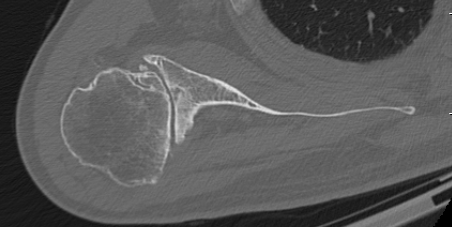

Walch classification glenoid morphology

Type A - centred humeral head, concentric wear, no humeral head subluxation

A1: minor central erosion

A2: major central erosion with humeral head protrusion

Type B - posterior subluxation of the humeral head, with biconcave glenoid and asymmetric wear

B1: narrowing of the posterior joint space

B2: biconcave glenoid with posterior rim erosion and retroverted glenoid

B3: monoconcave glenoid with > 15° retroversion or >70% posterior humeral head subluxation or both

Type C

C1: dysplastic glenoid with >25° retroversion

C2: biconcave, posterior bone loss, posterior translation of the humeral head

Type D: glenoid anteversion or anterior humeral head subluxation <40°

Type A2 Type B1

Type B2 Type B3

Type B3